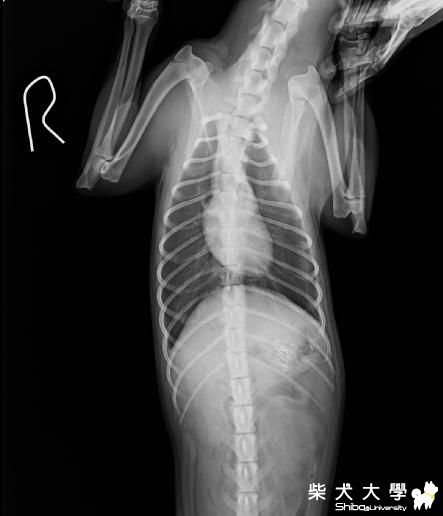

[醫療保健]骨盆骨折手術後 會有哪些後遺症(原發表者:天生神準)

目前竹筍已經手術完了還待在醫院吊點滴

預計明天要去帶他回來 自行照顧

竹筍還年輕 骨折的地方有拉回來接上了

有些地方還碎裂了

這樣他以後能正常走路嗎